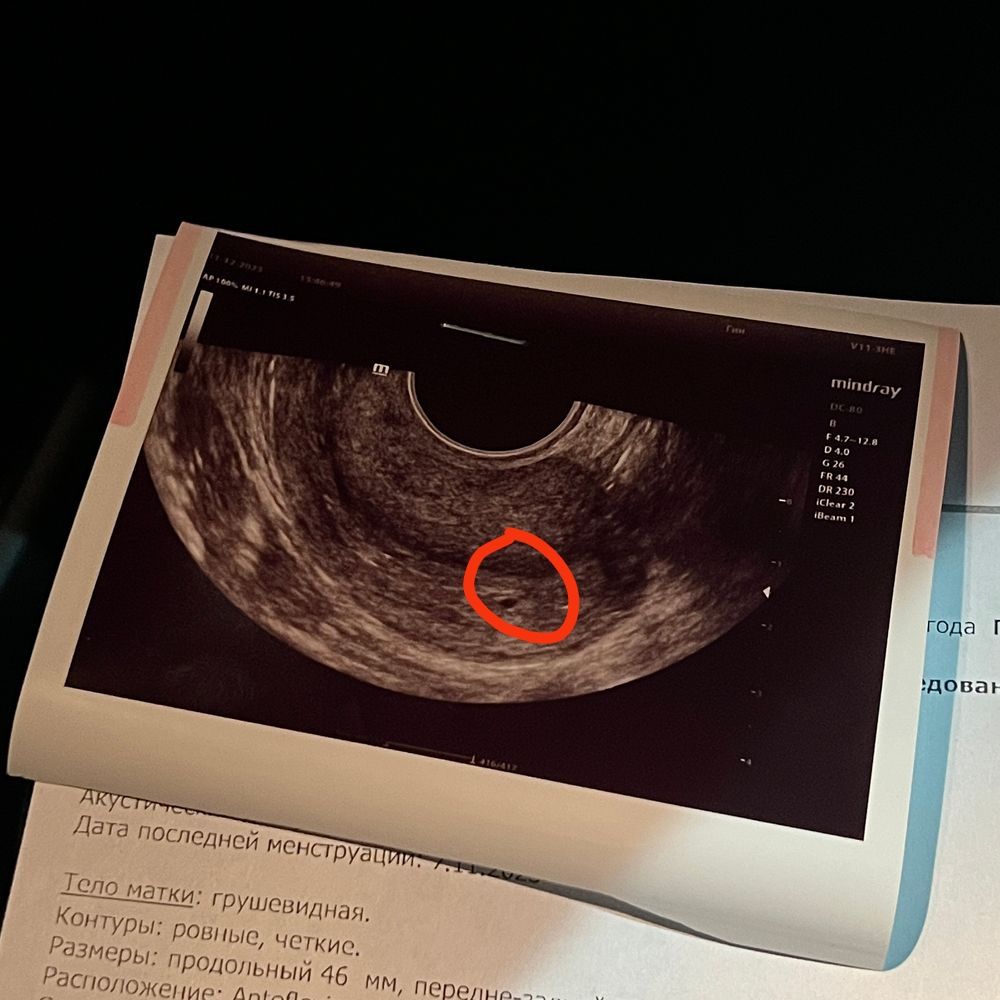

Изображение А это разве не оно? Что узист сказал?

Мария, она вообще сказала, что у меня поликистоз яичников под вопросом🥲 сказала ждите следующей недели, сейчас непонятно что это вообще за пятнышко и беременность ли это… Меня этот поход на узи вообще не обнадежил, скорее расстроил

Так вон же ваша беременность) девочки кружочком пообводили)

Lina, дада, я видела, но напрягает то, что какой то маленький размер и так сложно визуализируется на этом сроке😅 и слова узиста в целом напрягают

Мама девочки (2 года) Стамбул

Картина узи соответствует вашему сроку абсолютно, не переживайте). Я бы на первое узи рекомендовала идти не раньше 6-7 акушерских недель хотя бы (по месячным). Сейчас ещё яйцо крошечное, эмбриона там никто не увидит, а смысла ходить каждую неделю и высматривать рост яйца - никакого. Я была первый раз в 6 недель+1 день, тогда уже было сердечко.

Я вижу небольшое плодное яйцо примерно в центре. Все будет хорошо, постарайтесь не надумывать на ровном месте. Видите там есть кружочек чёрный? Такой немного овальный.. Вот ваше чудо😇

Мне на 25 дпо нашли яичко 2-3 мм, то что у вас на узи может быть яичком, а может быть веной, узисту виднее, подождите неделю, вы рано пошли